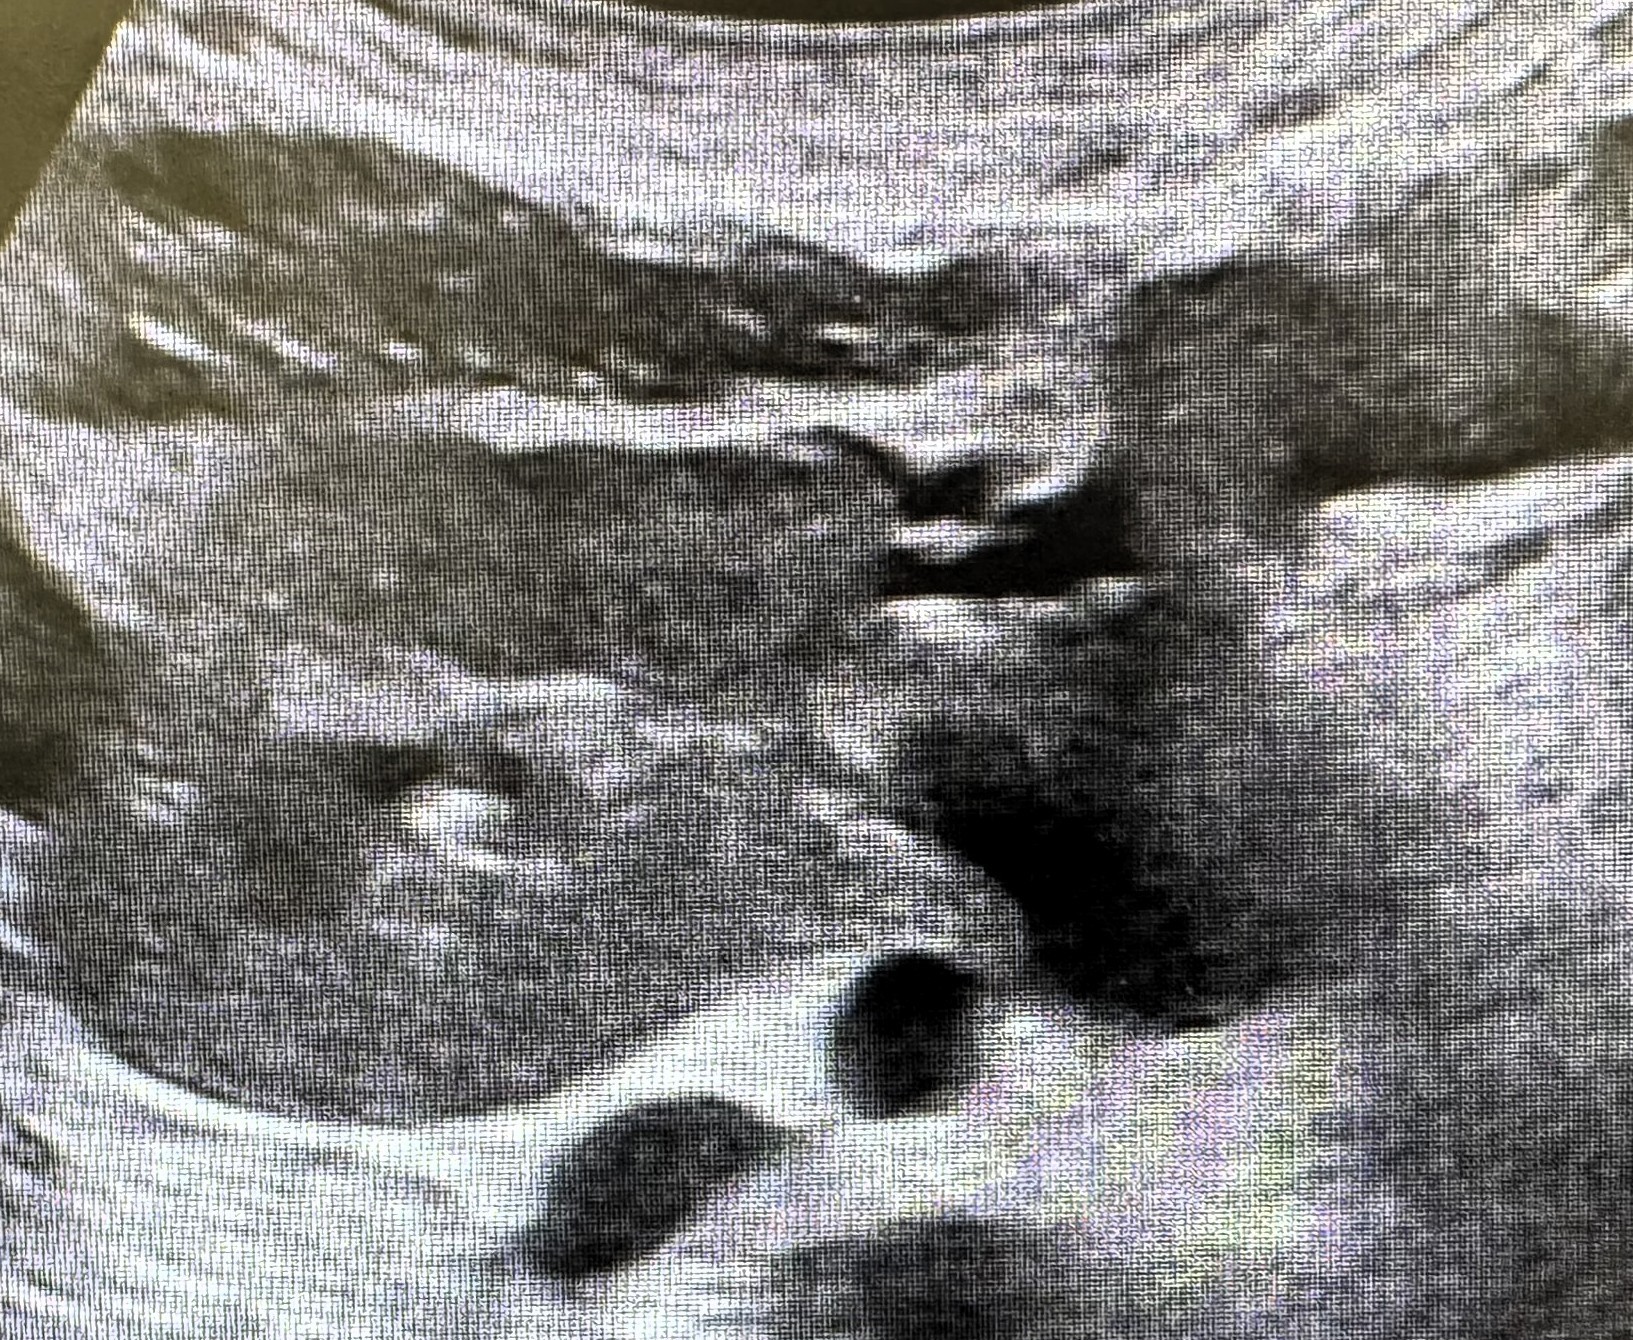

Se realiza eco abdominal: Riñón derecho ectopico, de localización paraórtica derecha, anterior a las asas intestinales, con pelvis renal orientada hacia anterior, de tamaño y grosor cortical normal, sin hidronefrosis. Riñón izquierdo de localización, morfología y tamaño normal, con buena diferenciación cortico-medular. Sin dilatación de la vía urinaria.

Conclusión: riñón derecho ectópico, congruente con la masa palpable.